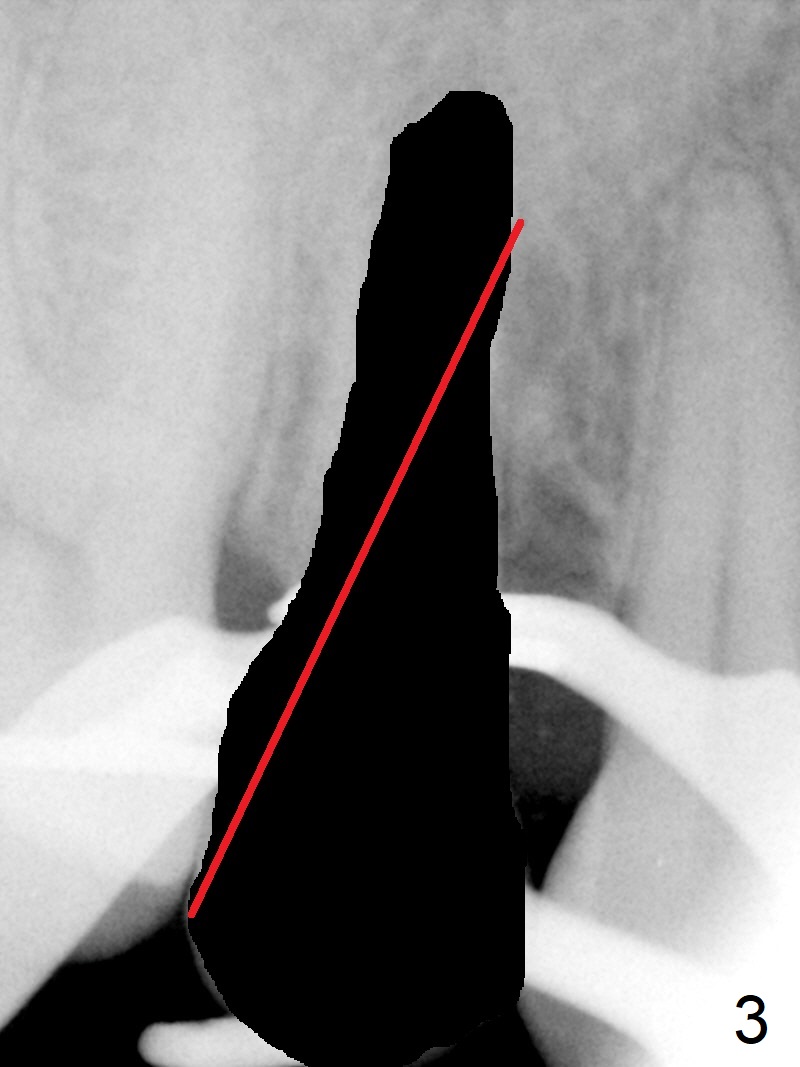

Seven years post RCT (Fig.1), the tooth #4 of a 65-year-old woman fractures subgingival palatally (Fig.2).  Since the root of the affected tooth is close to the tooth #3, osteotomy is established in the mesial slope of the socket (Fig.3).  Change the trajectory once the drill has penetrated the lamina dura of the socket (Fig.4).  The initial depth will be 20 mm for a 3.8x16 mm implant (Fig.5).